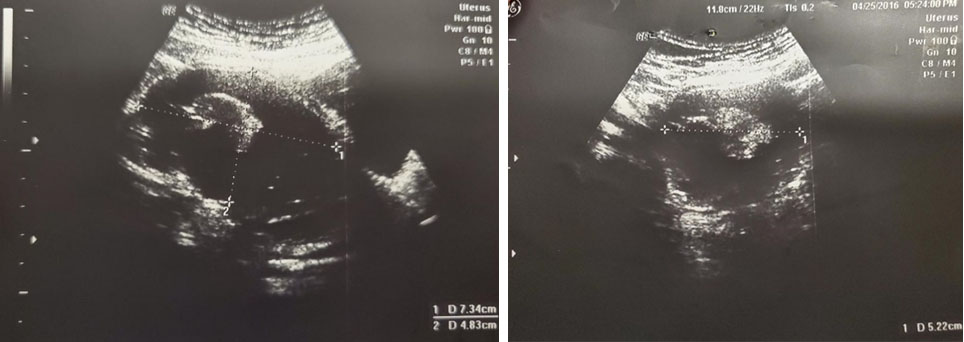

A 37-year-old lady presented with abdominal distension. She was referred to gynecology clinic and a CT was performed. Computed tomography in late 2015 showed a right adnexal cystic mass which measured 6.71 × 5.25 × 5.64 cm. Subsequent ultrasound showed a multiloculated right adnexal cyst with calcification 7.34 × 4.83 × 5.22 cm (Figure 6). Therefore, laparoscopic right ovarian cystectomy was performed in May 2016. Intra-operatively, the surgeons found a right ovarian cyst, which measured 7 × 6 × 5 cm. The cyst had sebaceous materials and hair inside. Pathology showed mature teratoma complicated with squamous cell carcinoma in situ and carcinoid. Her post-operative CA 125 level was 18 U/mL, compared to the pre-operative CA 125 level of 20 U/mL. She was advised to have right salpingo-oophorectomy (RSO) since small residual disease could not be ruled out. Laparoscopic RSO was done in February 2017. Pathology showed no evidence of malignancy. The pre-and post-operative 5-HIAA level was not available.

Figure 6: USG picture of the Case 2 ovarian tumor with echogenic components seen within. There is a multiloculated right adnexal cyst with calcification 7.34 × 4.83 × 5.22 cm.